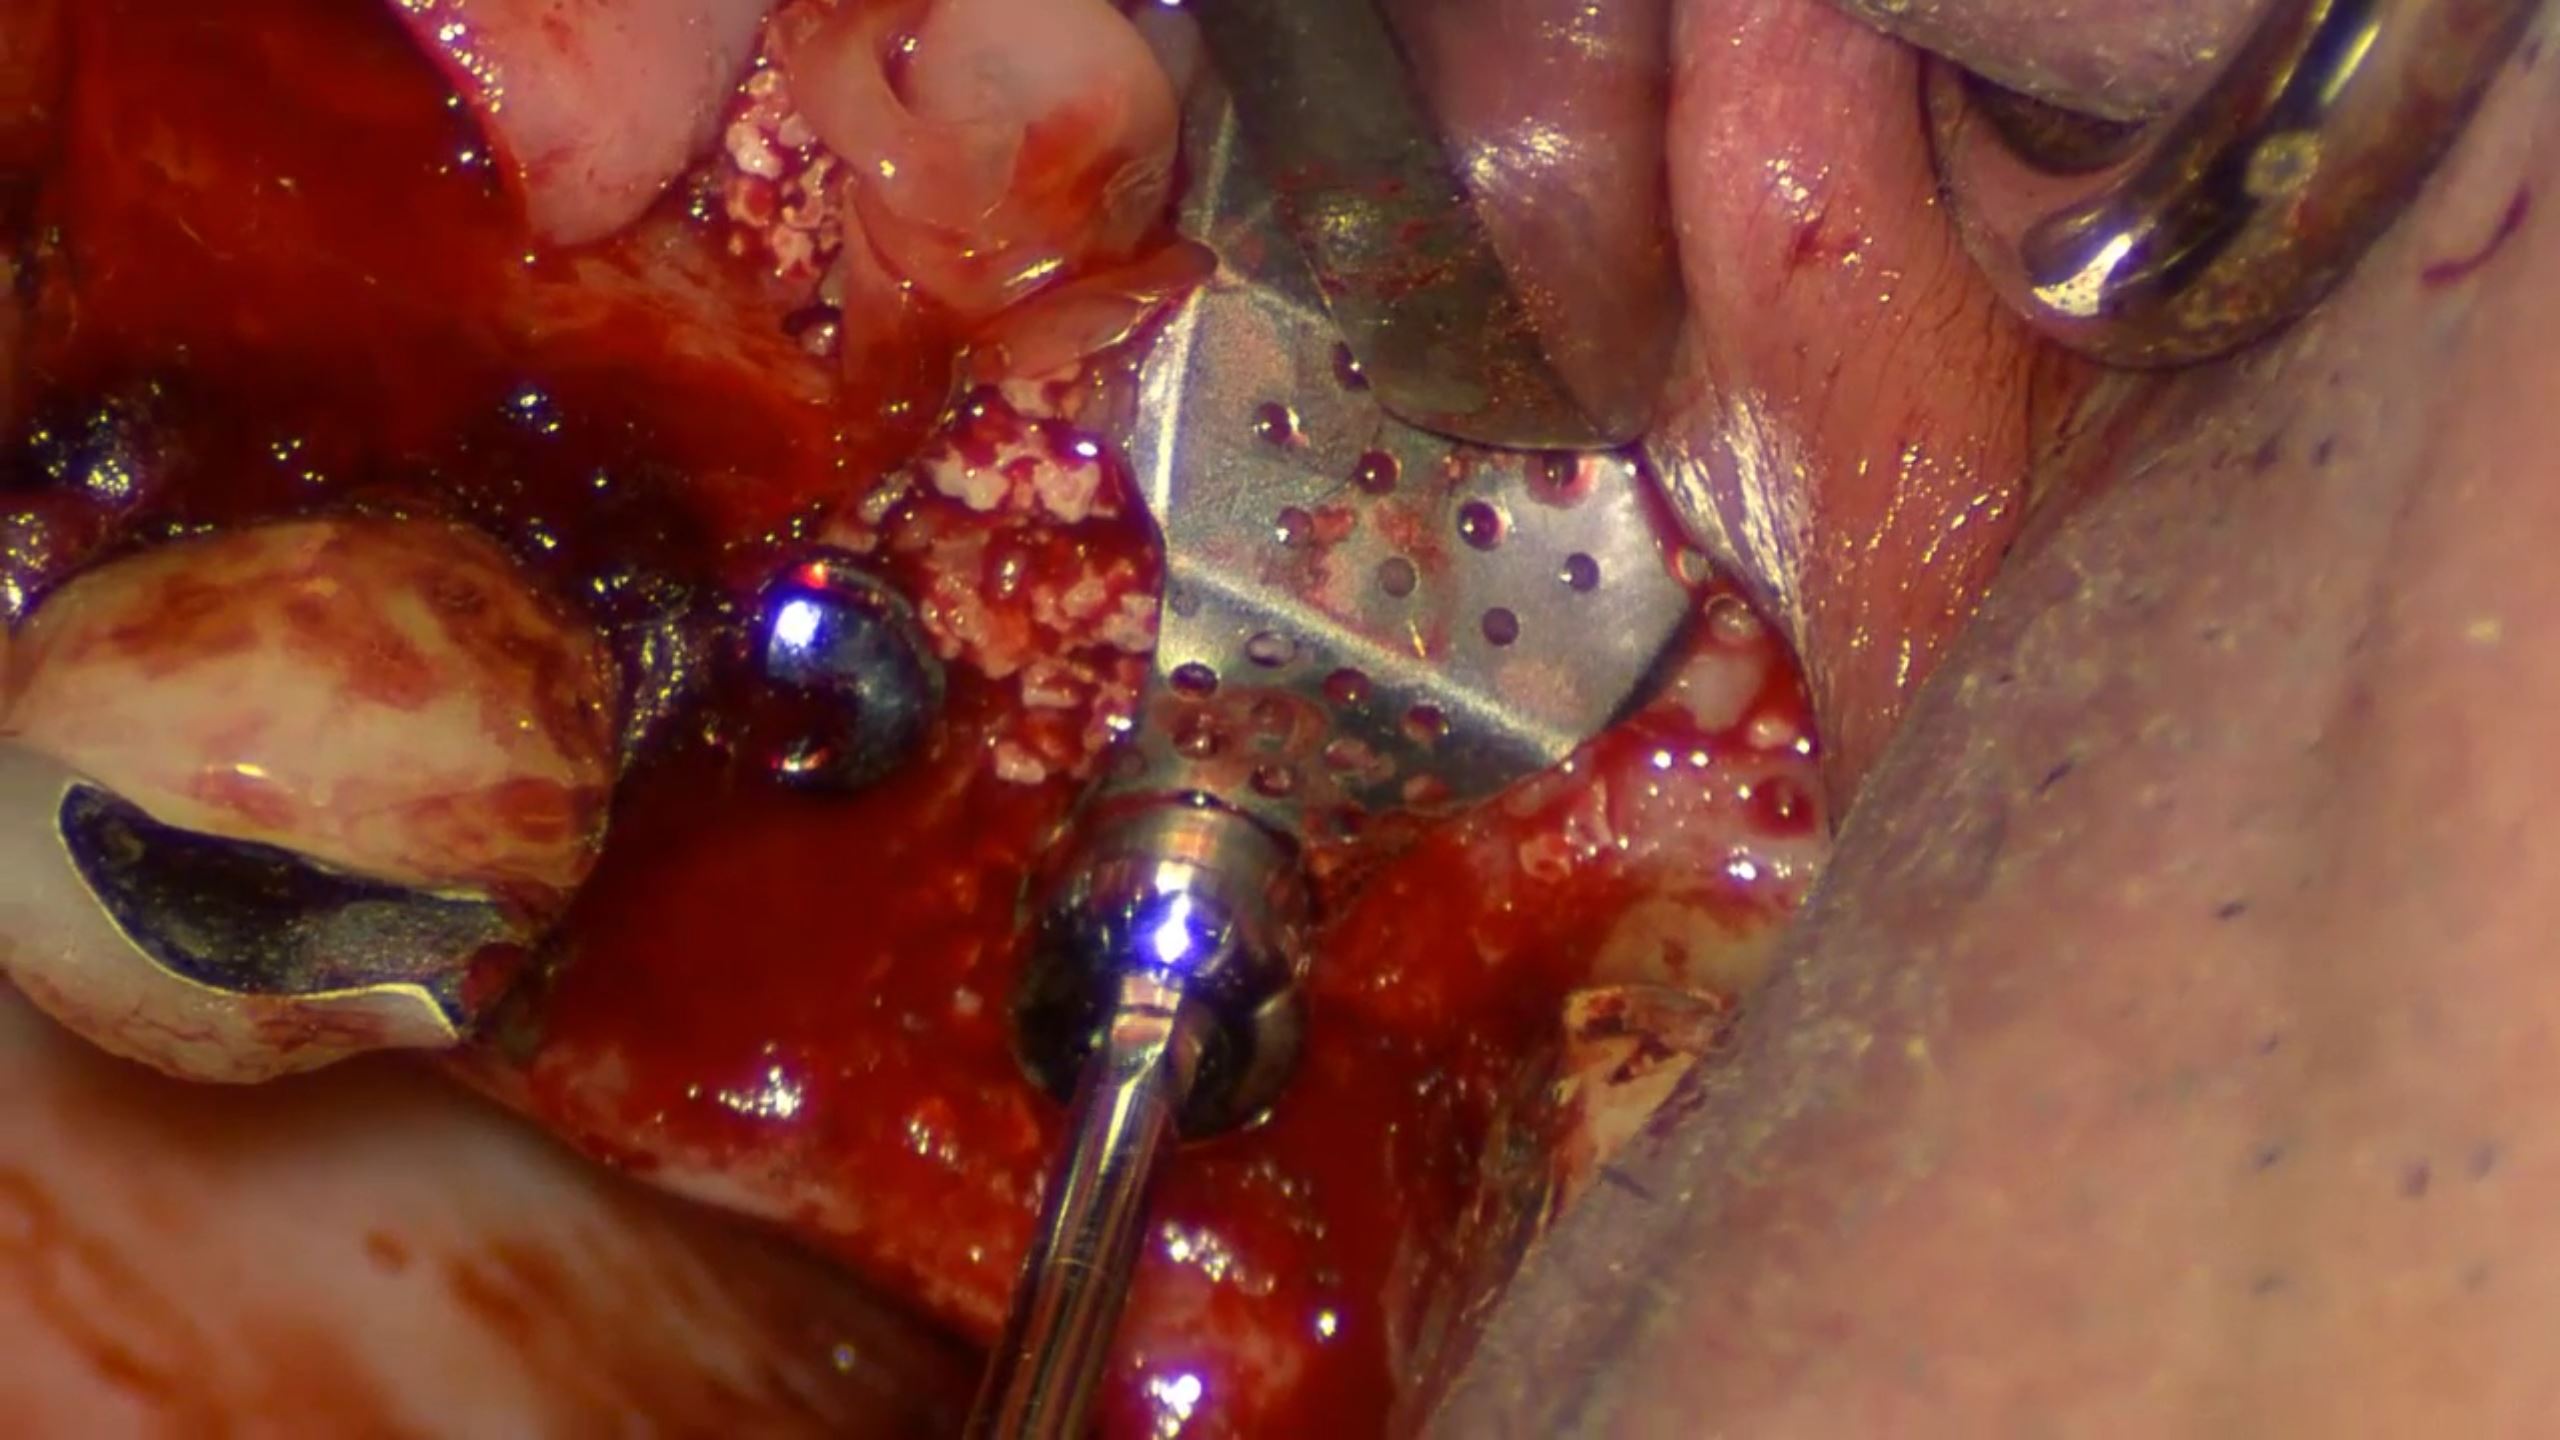

#11,#12,#23,#24 Root Membrane Technique with Digital R2GATE Surgery

Dr. Kwang Bum Park,Aesthetic zone,Digital Guided Surgery,Maxillary Anterior,Maxillary Posterior,#11,#12,#23,#24,Guided surgery,Root Membrane,AnyRidge,MiNi,R2GATE Guide,MEGA ISQ,Root Membrane Kit,R2GATE Surgical Kit(AnyRidge),Initial stability,Customized abutment,PMMA crown,Aesthetic…